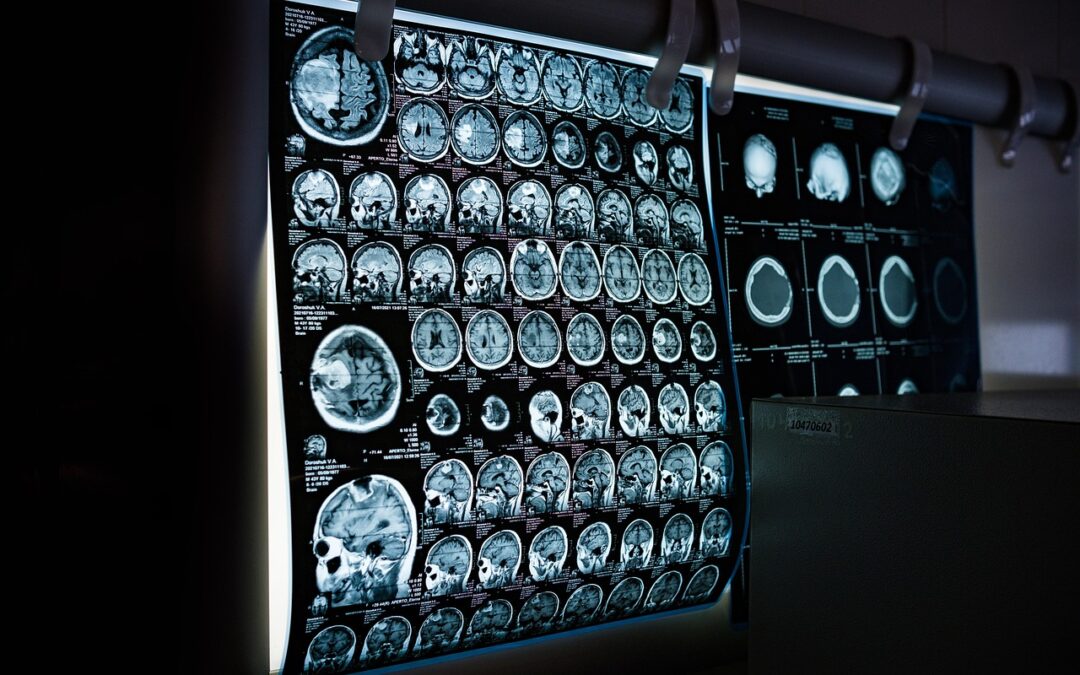

Posteriormente, el médico complementa esto con el electroencefalograma (EEG), que registra la actividad eléctrica del cerebro. Sin embargo, debes recordar que un EEG anormal por sí solo no diagnostica epilepsia; el resultado debe estar siempre respaldado por la ocurrencia de crisis repetidas.